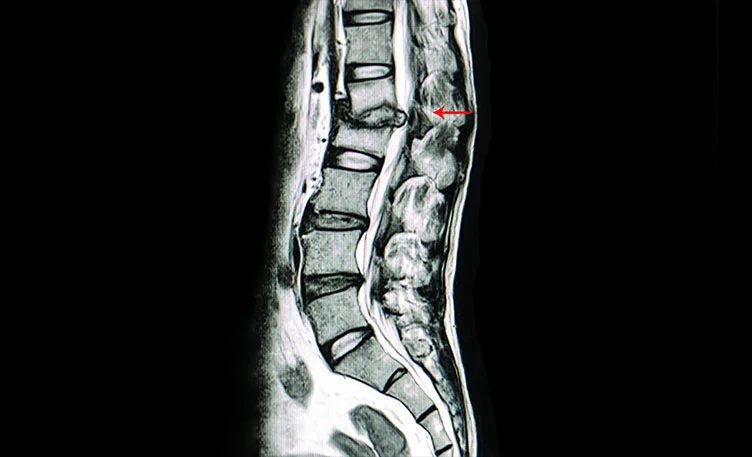

Diagnosis involves clinical evaluation, imaging tests like X-rays, MRIs, or CT scans, blood tests for inflammation markers (ESR, CRP), and tissue biopsy to confirm the presence of TB bacteria in the affected vertebrae.